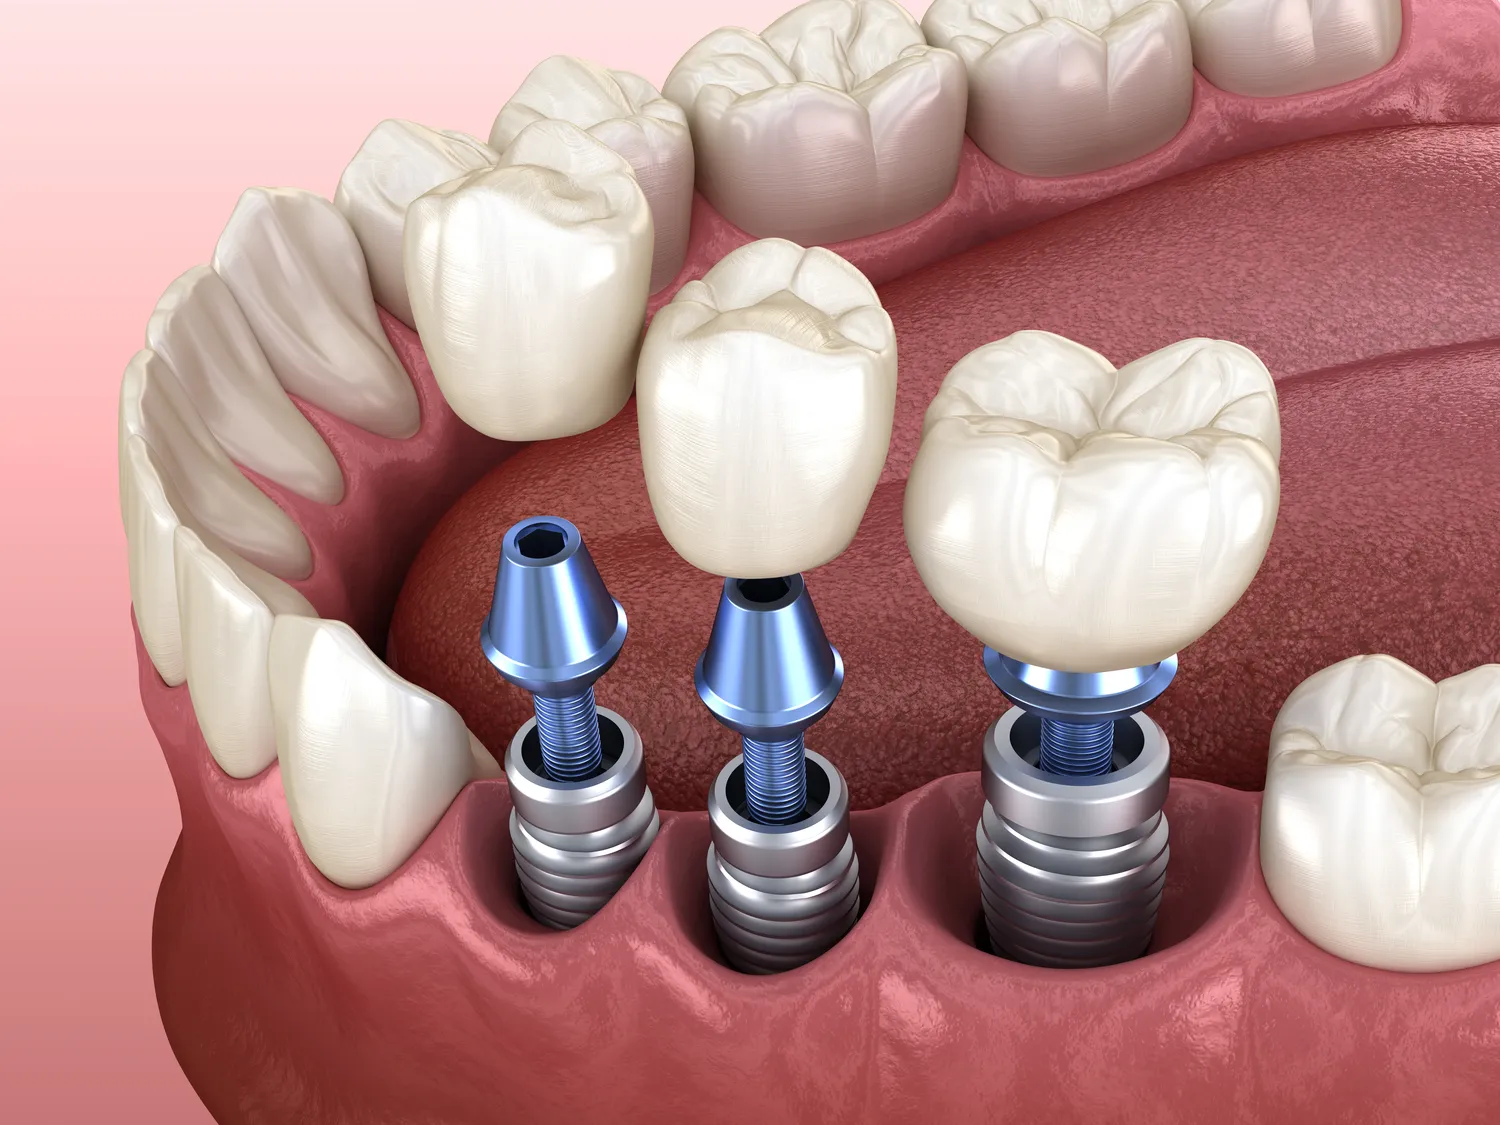

Proces wszczepienia implantów zębów w Turcji zazwyczaj rozpoczyna się od szczegółowej konsultacji, podczas której lekarz ocenia stan jamy ustnej pacjenta oraz wykonuje niezbędne badania diagnostyczne. Na podstawie tych informacji opracowywany jest indywidualny plan leczenia, który uwzględnia potrzeby pacjenta oraz rodzaj implantów, które będą użyte. Następnie przeprowadzany jest zabieg chirurgiczny polegający na wszczepieniu implantu w kość szczęki. Zabieg ten odbywa się w znieczuleniu miejscowym lub ogólnym, w zależności od skomplikowania przypadku oraz preferencji pacjenta. Po wszczepieniu implantu następuje okres gojenia, który może trwać od kilku tygodni do kilku miesięcy, w trakcie którego implant integruje się z kością. Po zakończeniu tego etapu następuje kolejna wizytacja, podczas której lekarz dokonuje oceny postępów gojenia i przystępuje do umieszczenia korony protetycznej na implancie.